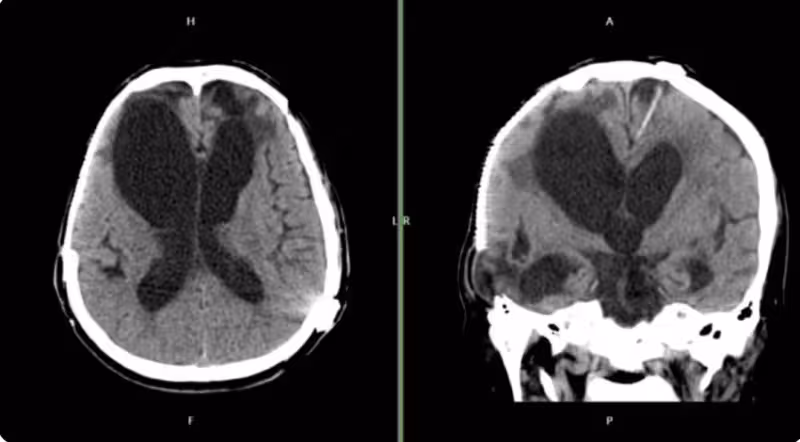

新光醫院急診醫學科醫師解釋,腦傷後常見「清醒期」:

「特別是硬腦膜下出血,患者可能先意識清醒數小時,等血腫擴大才突然惡化。這就是為什麼交通事故後即使當下沒事,也必須觀察72小時。」